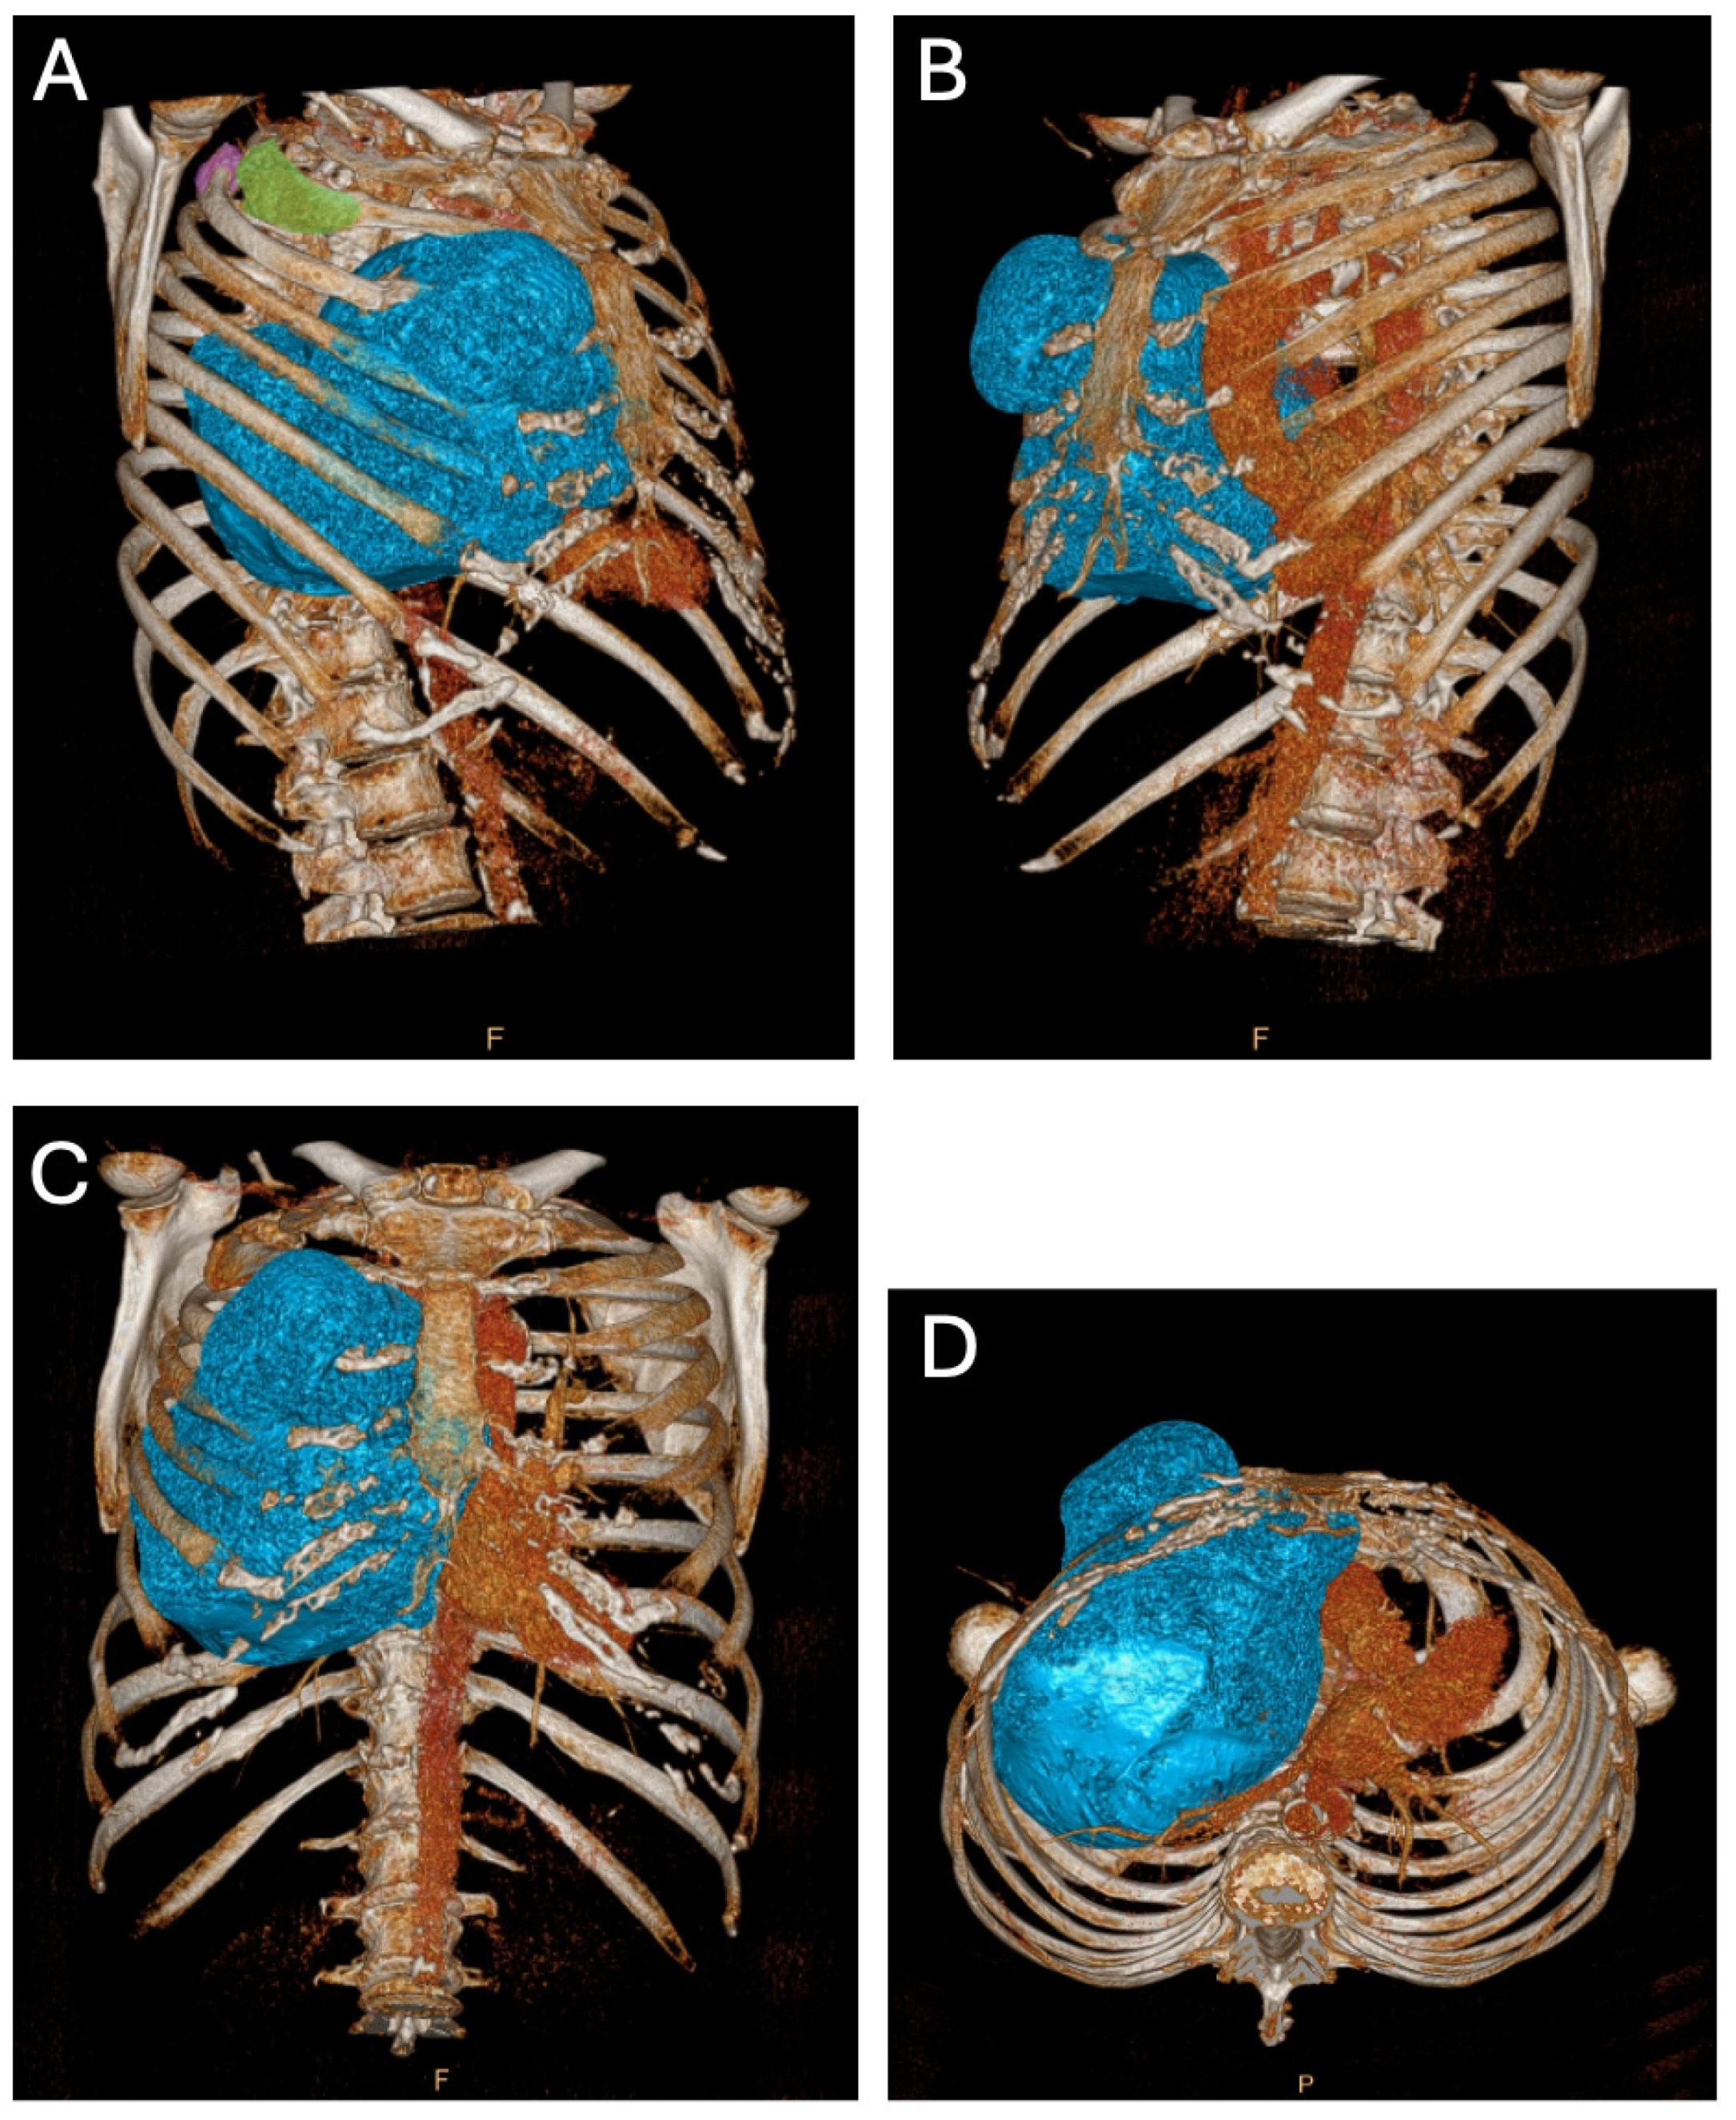

A computed tomography (CT) scan revealed three locations of FD: two minor lesions posterolateral in the second and third rib and one ventral in the third rib (Figure 2A), the latter being the most prominent lesion and responsible for the palpable extrathoracic mass (Figure 2B and Figure 3A). Its progression resulted in a mediastinal shift to the left (Figure 2C and Figure 3B) with compression of the superior caval vein and right atrium. Vascular displacement with compression of the right pulmonary artery was noticed, with dorsal displacement of the bronchus (Figure 2D).

Figure 2. Preoperative three-dimensional reconstruction of a computed tomography dataset. (A) Right ventral view. The significance of the major FD originating from the ventral third rib is shown with a blue overlay. The posterolateral FD in the third and second rib are depicted with a purple and green overlay, respectively. (B) Left ventral view. The prominent FD resulting from the ventral third rib is depicted with a blue overlay, with focus on the extrathoracic palpable part of the FD. (C) Ventral view. Significant mediastinal shift to left. (D) Caudal view. The mediastinal shift is clear with posterior vascular and bronchial displacement.